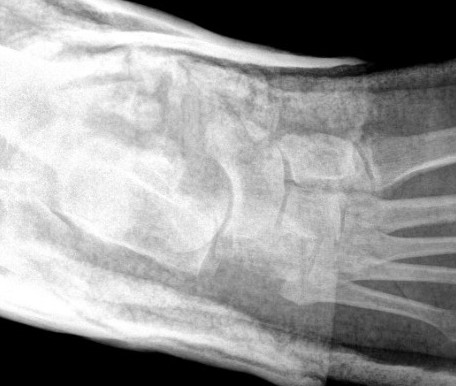

Chopart joints

- talonavicular joint

- calcaneocuboid joint

Ligamentous +/- fracture dislocations

Fractures - trans-navicular / trans-cuboid